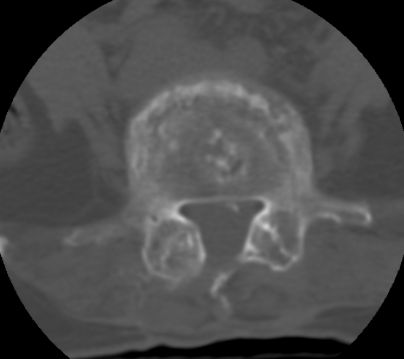

以下是引用余辉在2007-9-4 21:00:00的发言:[br]椎体棘突有点异常(像是被切割了),不知有否手术史,如椎体融合术等。单纯的退行性变可以出现椎间隙变窄,但同时一般会出现椎体上下缘的硬化增生,且椎体间完全融合的机率更小,本例椎体完全融合且椎体上下皮质缘破坏掉了,如果没有手术史,就应该考虑椎间盘炎性病变了,且椎体棘突及棘间韧带的变化也并不是不支持这个,多数小关节也融合了,且其形态也容易让人联想到如强脊炎及类风关等病变。[br][br][本贴已被 余辉 于 2007-9-4 21:03:55 修改过]

以下是引用chry3在2007-9-4 20:42:00的发言:[br]椎间盘病史?是什么样的病史,无双下肢放射痛,那就不是椎间盘突出了。是感染、什么性质的?[br]从图象看椎间隙消失,椎间盘组织未见,锥体滑脱是因为椎间盘溶解造成的[br]l4、5椎体骨质结构未见异常,l5上缘是l4的长期压迫所致[br]还是考虑椎间盘感染,结核。[br]